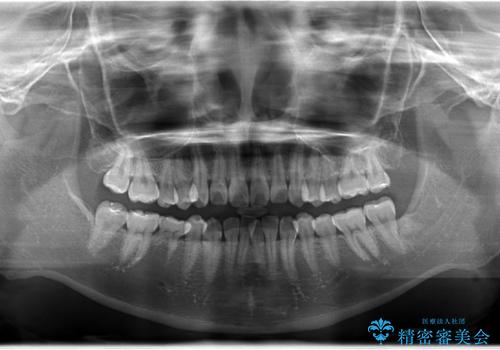

- 患者様は、右下第2小臼歯(5番)の先天欠如により乳歯が残存している状態でした。

加えて、**下顎前歯部に叢生(歯のがたつき)**が見られ、審美的・機能的な改善を希望されて来院されました。

診査の結果、乳歯は長期間機能していましたが、将来的な脱落のリスクが高く、インプラントによる永久歯の補綴が望ましいと判断しました。

また、欠損部にインプラントを埋入するには、前後の歯の傾斜改善とスペース確保のための矯正治療が必要でした。